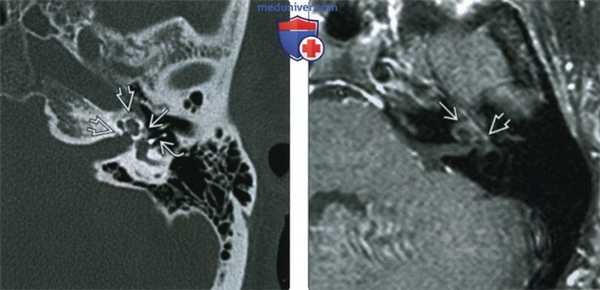

Тимпанальный и кохлеарный отосклероз: А. и Б. Аксиальная. В. и Г. Коронарная КТ; Д. Аксиальная МРТ в режиме Т1 после контрастирования.

Подножная пластинка правого стремени утолщена (А и В, стрелки). Грубые спогиозные изменения проникают через костную капсулу (Б и Г, стрелки).

При МРТ выявлено усиление активных очагов отосклероза. Рецидив отосклероза после стапедэктомии: А. Аксиальная, Б Коронарная КТ.

Металлический протез проходит от длинного отростка наковальни к овальному окну, выглядящему не обтурированным.

Медиальная часть протеза в выгодном положении, но фиксированная большим очагом, облитерирующим нишу овального окна (стрелка).

Внутри капсулы улитки обращают на себя внимание отоспонгиатические изменения.